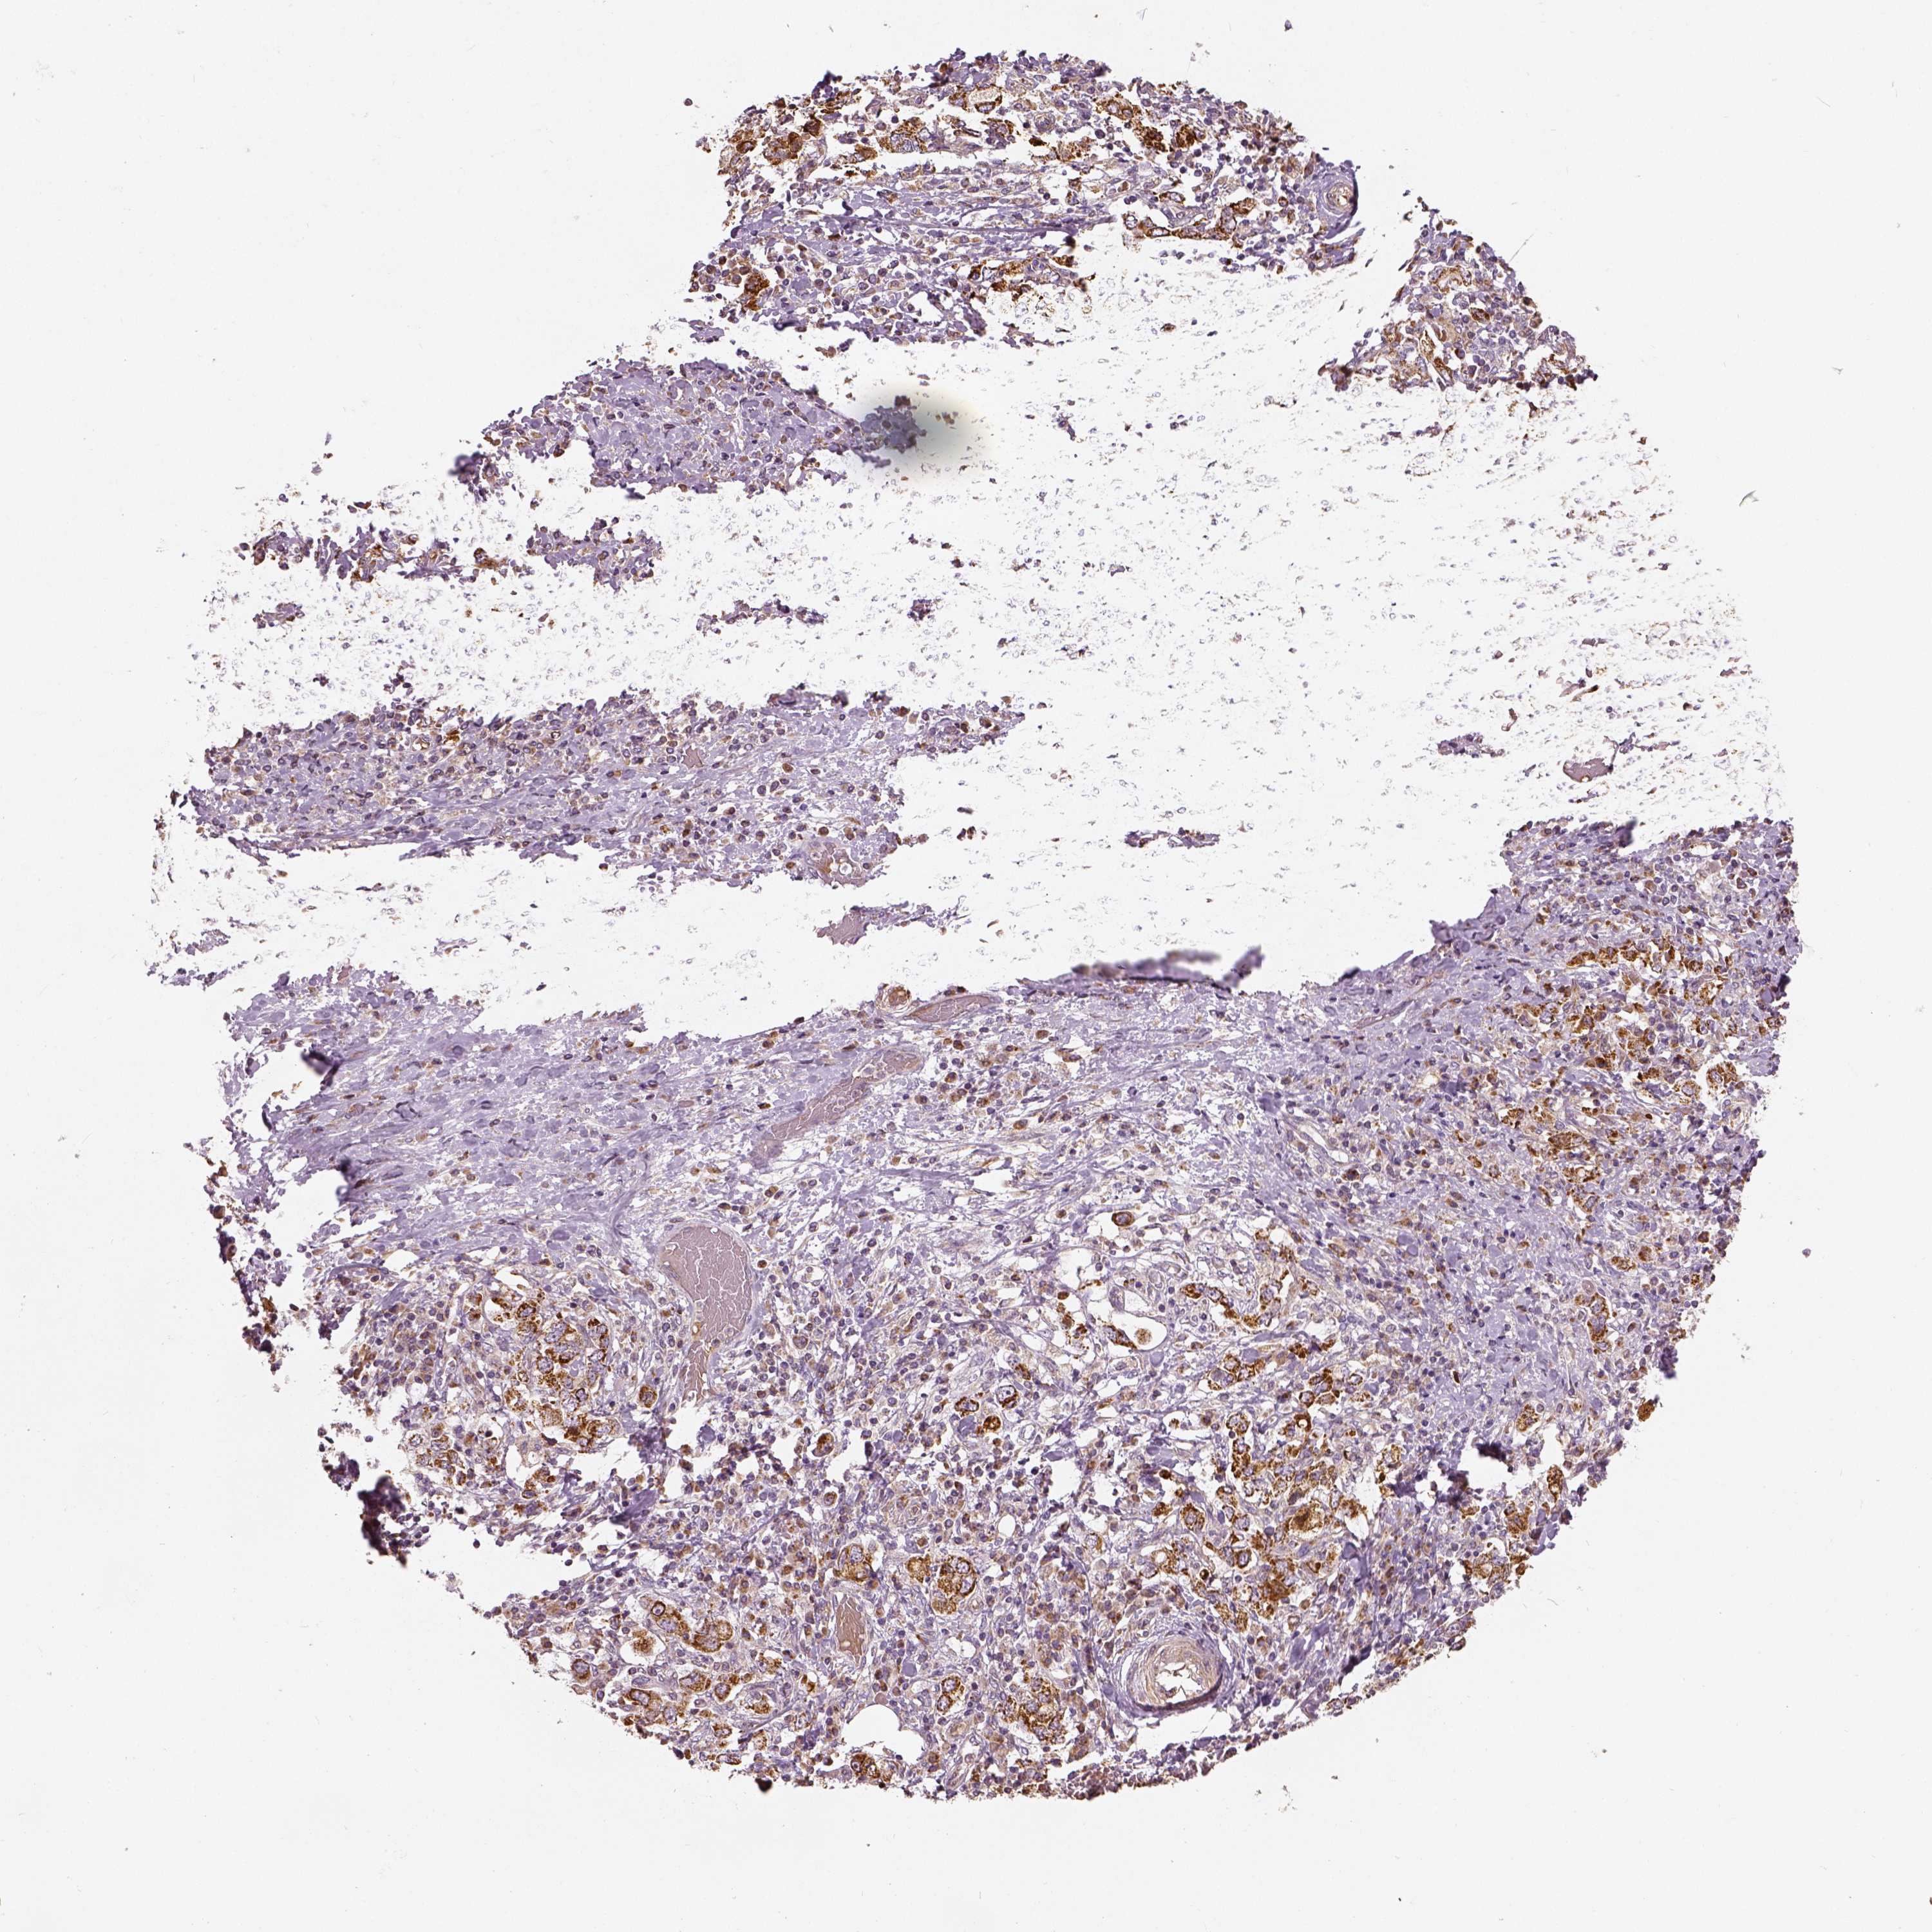

STOMACH CANCER - Protein expressioni

A mouse-over function shows sample information and annotation data. Click on an image to view it in a full screen mode. Samples can be filtered based on level of antibody staining by selecting one or several of the following categories: high, medium, low and not detected. The assay and annotation is described here.

Note that samples used for immunohistochemistry by the Human Protein Atlas do not correspond to samples in the TCGA dataset.

Antibody stainingi

Antibody staining in the annotated cell types in the current human tissue is reported as not detected, low, medium, or high, based on conventional immunohistochemistry profiling in selected tissues. This score is based on the combination of the staining intensity and fraction of stained cells.

Each image is clickable and will lead to virtual microscopy that enables deeper exploration of all samples and also displays staining intensity scores, fraction scores and subcellular localization as well as patient and tissue information for each sample.

Antibody HPA036978

Antibody HPA036979

Antibody CAB068215

Staining

High

Medium

Low

Not detected

Intensity

Strong

Moderate

Weak

Negative

Quantity

>75%

75%-25%

<25%

None

Location

Nuclear

Cytoplasmic/membranous

Cytoplasmic/membranous,nuclear

Adenocarcinoma, NOS